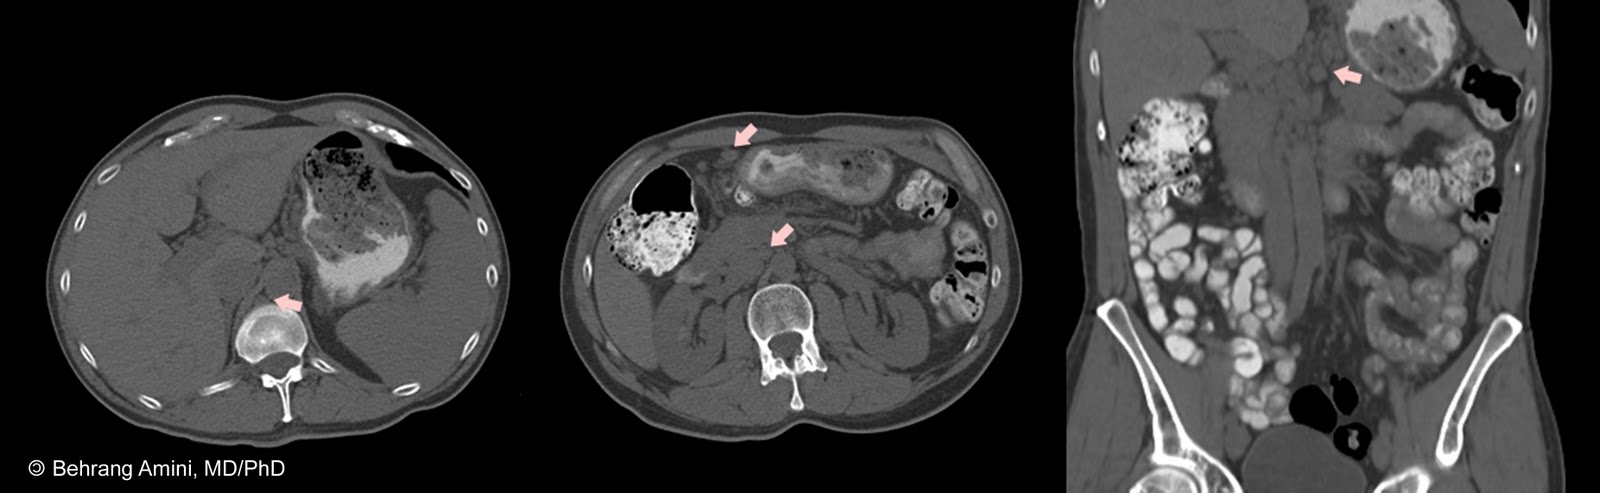

Coronary angiography, the standard reference technique for diagnosing coronary aneurysms, is invasive and expensive. Further, by only allowing depiction of flow within the lumen it may underestimate the true size of the aneurysm.

Coronary CTA is noninvasive and allows accurate assessment and characterization of the aneurysm, providing information on size, location and the amount of thrombus and calcification.